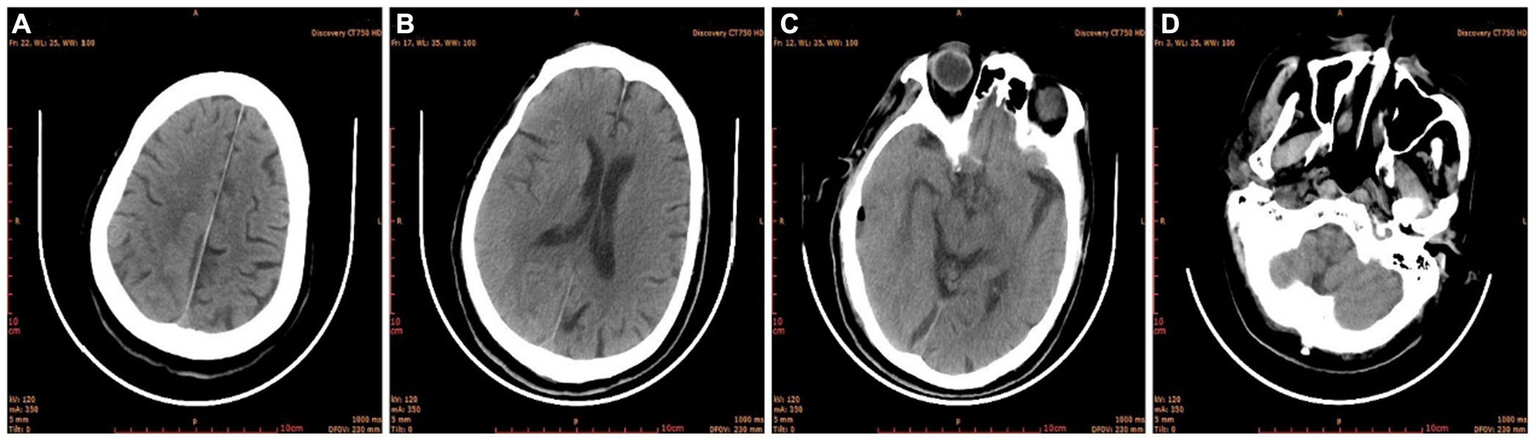

The condition of the right eye steadily improved 6 h after the first surgery. Multiple brain abscesses were discovered during postoperative MR examination (Figure 3). On the 3rd postoperative day, the intracranial abscess was punctured and drained under monitored anesthesia care (MAC). Blood and pus samples were subjected to a drug sensitivity test and bacterial culture, respectively. Postoperative recovery went well. After the second surgery, the motor function and muscle strength of the left upper and lower limbs gradually improved. There were no signs of widespread infection. He was discharged from the hospital on April 11 after a CT scan showed no abnormalities (Figure 4).

Figure 4

Brain CT before discharge. (A) Semi-oval central level; (B) lateral ventricular body level; (C) cerebral base level; (D) skull base level.